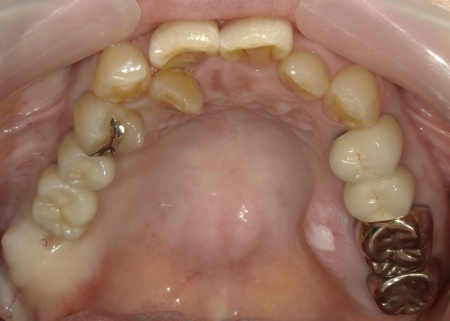

治療前

| カウンセリング・診断結果 | 拝見したところ、右上の歯には、欠損部位前後の歯を土台として橋を渡すように連結した被せ物「ブリッジ」が装着されていました。 しかし、土台となっている手前の歯(第2小臼歯)は歯根が割れており、同じく土台となっている奥の歯(第2大臼歯)は歯根の先に膿の袋ができる「根尖病巣(こんせんびょうそう)」が認められます。 さらに、ブリッジ部位の歯茎は腫れ、痛みもあるとのことでした。 かかりつけの歯科医院では、細菌感染を抑える薬を飲んだり、歯を少し削って噛み合わせを調整したりして様子を見ていましたが、口腔内の状態が改善せず、次は抜歯をする必要があると説明を受けたそうです。 また抜歯後に歯を補う方法のひとつにインプラント治療がありますが、患者様の場合は治療に必要な骨量が確保できないため難しいとされ、取り外し式の入れ歯になるとのことでした。 患者様はかかりつけ医からの説明が十分でないと感じていたため、当院にセカンドオピニオンで来院されています。 以上のことから、まずはブリッジ周辺の治療を行ったのち、欠損部を補う治療方法をしっかりと検討する必要があると診断しました。 |

| 行ったご提案 ・治療内容 | 痛みが出ているブリッジ周辺の治療として、ブリッジの土台となっていて、歯根が割れている手前の歯(第2小臼歯)は抜き、根尖病巣を発症している奥の歯(第2大臼歯)は、根管治療を行います。 根管治療とは、感染した神経を取り除いて、歯根内部を清掃・消毒する治療方法のことです。 抜歯と根管治療を行ったあとは、欠損部を補うために、2本のインプラントを埋入する方法を提案しました。 インプラントを埋入するために必要な骨量が足りない場合は、鼻の空洞(上顎洞)の粘膜を少しずつ押し上げて骨を増やす「ソケットリフト」を併用することもお伝えしています。 インプラント治療のメリット インプラント治療のデメリット それぞれの方法について丁寧にお伝えした結果、治療に同意いただきました。 まずは、右上手前の歯(第2小臼歯)を抜きました。 抜歯後は、インプラント治療を行うために、歯を支える骨(歯槽骨)の回復を待つ必要があり、最低でも6ヶ月を要します。 約2ヶ月後、インプラントと骨が結合したことを確認して、右上奥歯2本の仮歯を作製し、手前の歯槽骨が再生するまで経過観察を継続します。 約4ヶ月後、歯槽骨の再生が確認できたため、もう1本のインプラントを埋入しました。 当院のインプラント治療は、施術の安全性と長期的な使用を可能にすることを優先して治療を行うため、通常は抜歯後に歯槽骨の治癒を待ってからインプラントの埋入を行っています。 右上奥歯2本に仮歯が入り、噛み合わせが安定した状態になったため、根尖病巣を発症している右上奥歯の治療を開始します。 また、インプラントに装着する人工歯を作製する前に、歯科医院で歯を白くするオフィスホワイトニング治療を希望されたため、治療期間がやや長くなっています。 最後に、完成した人工歯を装着し、見た目や噛み合わせに問題がないことを確認して、治療を終了しています。 |